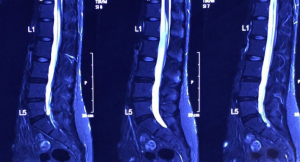

Illustrated MR 1, MR2 – Severe lumbar disc herniation in the fourth and fifth segments in August 2011.

Illustrated MR 3, MR 4- In January 2016, the degree of herniated disc has been greatly improved, and the previously compressed part of the nerve root has also disappeared.